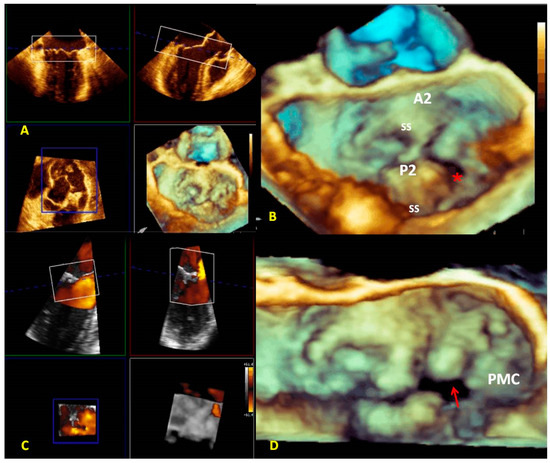

3.1. Anatomical Characterization